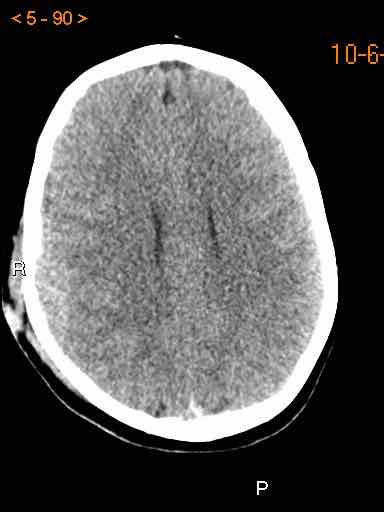

Tụ máu dưới màng cứng đồng tỷ trọng

Khi tụ máu dưới màng cứng tiến triển theo thời gian, tỷ trọng của khối tụ máu sẽ giảm dần và có thể tương đương với tỷ trọng của nhu mô não, khiến việc phát hiện tổn thương trở nên khó khăn.

Đây là trường hợp tụ máu dưới màng cứng đồng tỷ trọng rất khó phát hiện (các mũi tên).

Lưu ý rằng ở mức cắt cao hơn có tụ máu dưới màng cứng hai bên.